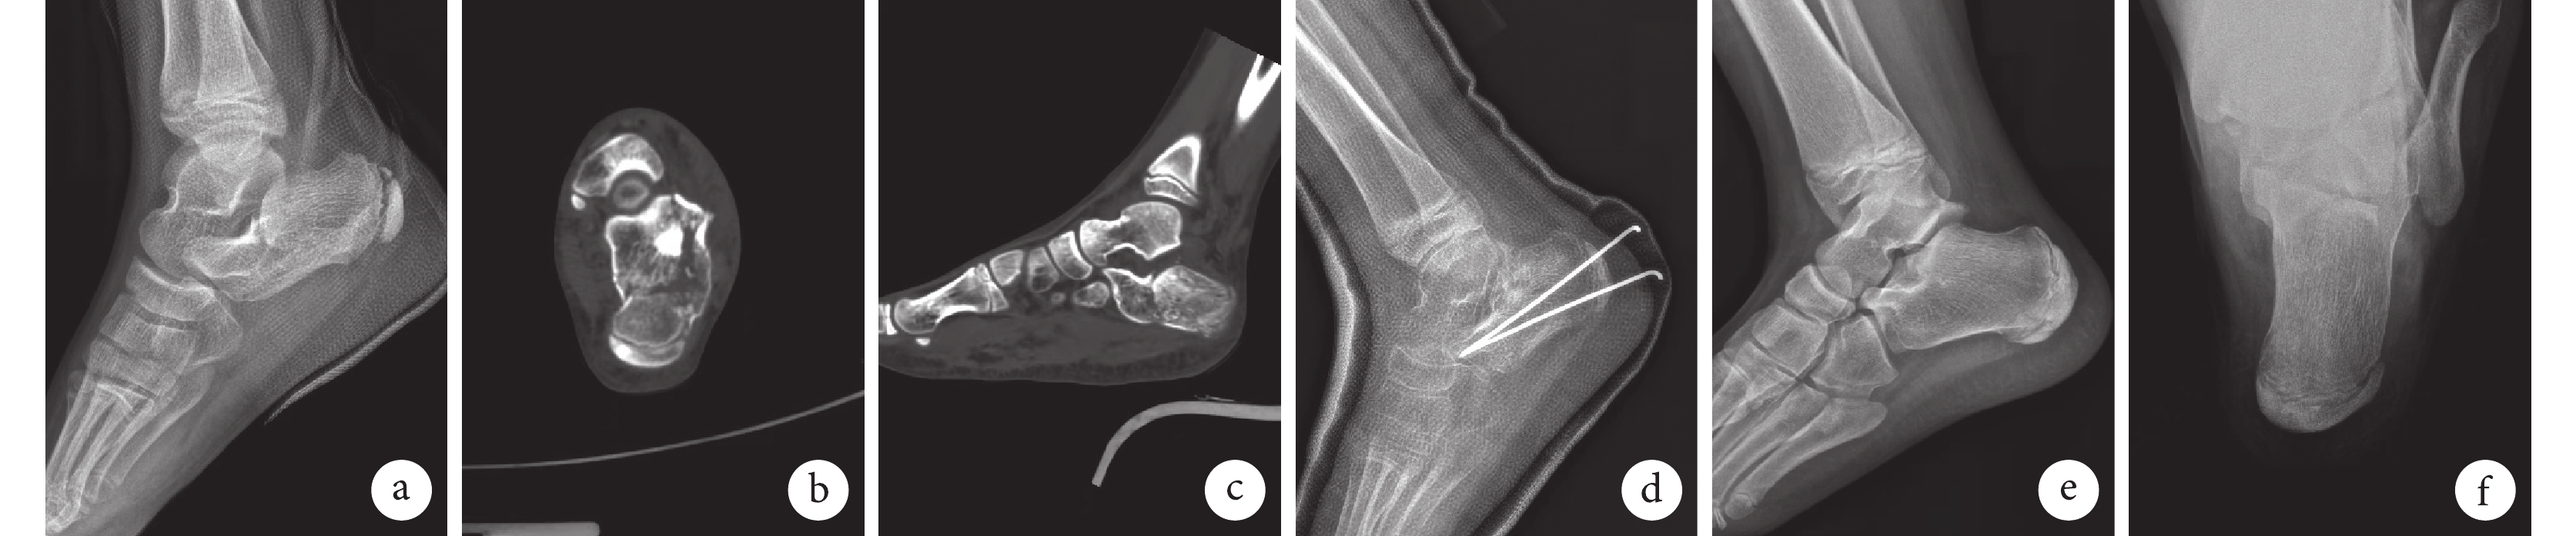

a~c. 術前側位X線片以及CT示左側跟骨骨折,后關節面塌陷;d. 術中見左側跟骨關節內骨折移位距離約2 mm;e、 f. 術后4個月側位及軸位X線片示骨折愈合,Gissane角及Böhler角恢復正常;g、h. 術后13個月取出鋼板后側位及軸位X線片。

Figure1. A 10-year-old girl with intra-articular fracture of the left calcaneus (Sanders type Ⅲ) in the plate groupa-c. Preoperative lateral X-ray film and CT showed the left calcaneal fracture and posterior articular surface collapse; d. The intra-articular fracture of the left calcaneus was displaced about 2 mm during operation; e, f. Lateral and axial X-ray films at 4 months after operation showed that the fracture healed, and the Gissane angle and Böhler angle returned to normal; g, h. Lateral and axial X-ray films after removing the plate at 13 months after operation

術后鋼板組1足發生切口皮膚壞死,經封閉式負壓引流、換藥后愈合;其余患兒切口均Ⅰ期愈合。兩組患兒均獲隨訪,隨訪時間12~39個月,平均19個月。X線片復查示兩組骨折均愈合,無延遲愈合;鋼板組愈合時間為(2.65±0.71)個月,克氏針組為(2.24±1.38)個月,差異無統計學意義(t=1.161,P=0.253)。X線片復查示,末次隨訪時跟骨Gissane角、B?hler角均恢復正常,組內手術前后比較差異均有統計學意義(P<0.05),組間手術前后差值比較差異無統計學意義(P>0.05),見表1。鋼板組于術后11~22個月,平均16.8個月取出鋼板。見圖1、2。